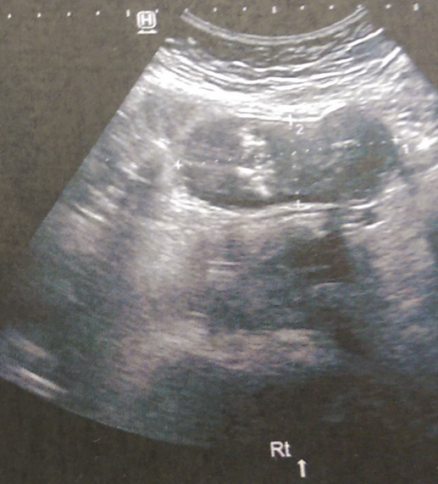

Πυελικό υπερηχογράφημα – Απλή κύστη αριστερής ωοθήκης (Ευγενική παραχώρηση Dr. V. Penopoulos)